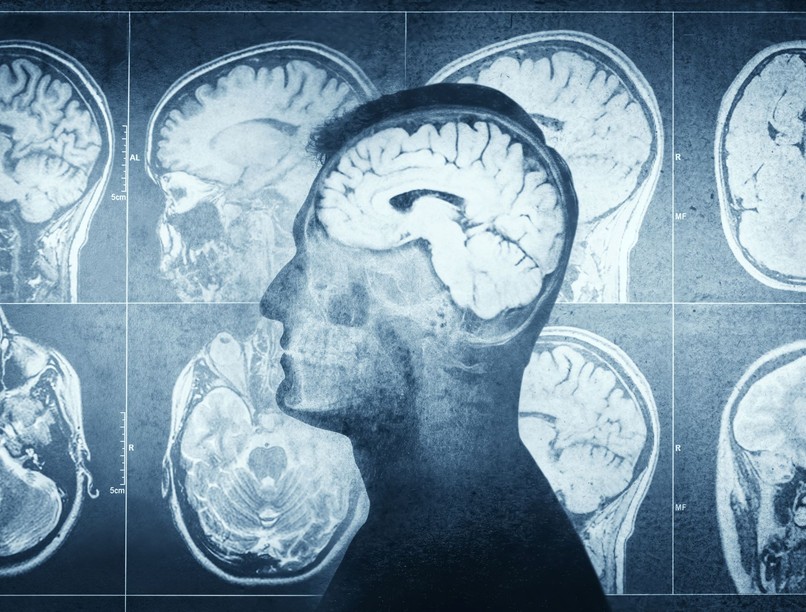

A Floridai Egyetem kutatói középkorú és idősebb felnőttek agyát vizsgálták korszerű MRI-felvételek és gépi tanulási módszerek segítségével. Ezekkel az eszközökkel meg lehet becsülni az úgynevezett agyéletkort, vagyis azt, hogy az agy szerkezete és működése mennyire felel meg az adott naptári életkornak.